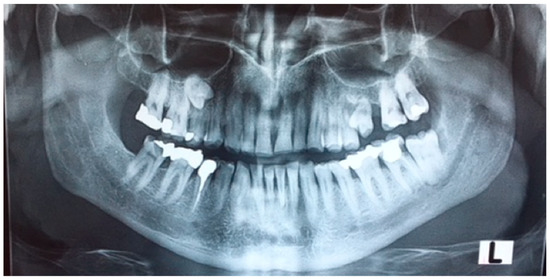

2.2. Case 2

Case 2 Presentation